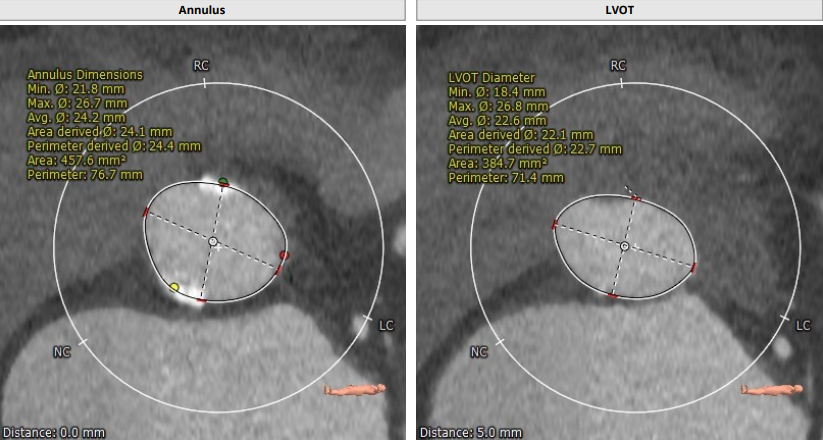

CT报告评估:

Annulus:24.4mm,LVOT:22.6mm,Asc.Ao:43.4mm,STJ:30.7mm。

瓣环结构及钙化情况:患者为TYPE 1型二叶瓣,瓣环及左室流出道呈上宽下窄型结构,钙化积分为529,主要集中于无冠窦,从基底部开始延申至左右融合处及无冠窦游离缘,整体窦部空间合适。